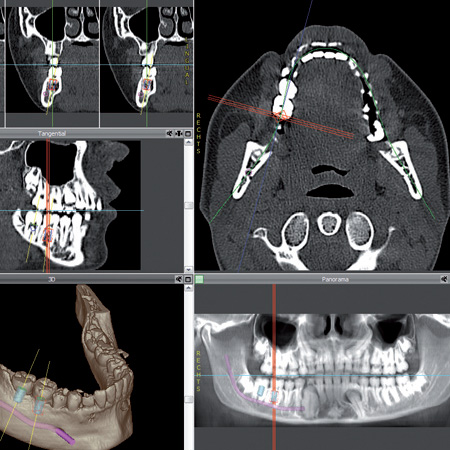

Unser Team ist spezialisiert auf minimal invasive Implantationen. Sie sind

für Patienten zeitsparender und deutlich angenehmer. Die

computerunterstützte Implantologie ermöglicht eine besonders schonende

Vorgehensweise.